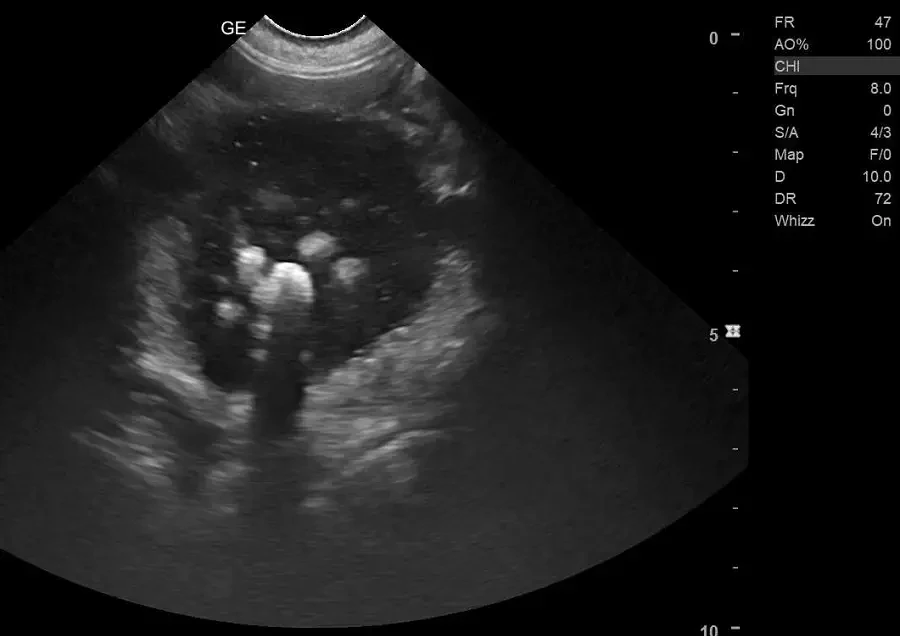

Kamienie moczowe w pęcherzu buldoga angielskiego

Tym razem naszym pacjentem był Gucci – prawie dwuletni buldog angielski. Trafił do kliniki, ponieważ właściciele zauważyli, że przestał oddawać mocz, ponadto…